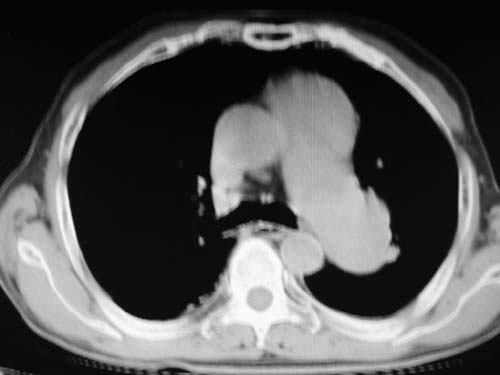

男,80岁

肺a高压征[左肺a狭窄?];肺,胸膜tb

右肺上叶结核;左肺门占位?建议增强扫描.

左下肺静脉扩张,原因?建议cta

看起来有点像血管。建议增强。

左肺动脉异常增粗,建议增强。

1)考虑肺动脉狭窄。2)右肺上叶继发性肺结核。3)右侧胸膜增厚、钙化,左侧胸膜反应。

应该是增粗血管,建议增强。

肺动脉瘤。建议先行ct增强扫描

左肺动脉异常增粗,考虑肺动脉狭窄可能。

右肺上叶继发性肺结核。

右侧胸膜增厚、钙化,左侧胸膜反应。

左肺动脉异常增粗,建议ct增强,排除肺门肿瘤

右侧胸膜增厚、钙化,左侧胸膜反应

双肺陈旧性病变,左肺动脉高压.

1)考虑左肺动脉瘤可能性大,建议增强。2)右肺上叶继发性肺结核。3)右侧胸膜增厚、钙化,左侧胸膜反应。

肺动脉段突出,左右肺门不等大,左肺门明显增大,肺动脉干及左肺动脉明显增宽,考虑先天性肺动脉狭窄瓣膜狭窄型。

)考虑肺动脉扩张,右心室增大,主动脉弓段正常位弓后段明显变小(不会是动脉导客未闭吧,不知患者有何症状病史)0。2)右肺上叶继发性肺结核。3)右侧胸膜增厚、钙化,左侧胸膜反应。

右肺上叶尖段结核;左肺下叶占位?建议增强扫描。右侧胸膜增厚;右肺局限性肺气肿。

结合患者年龄,不除外左下肺扩张性动脉瘤,建议胸透是否有扩张性博动,以便确诊。

肺动脉高压,左肺动脉瘤样扩张。